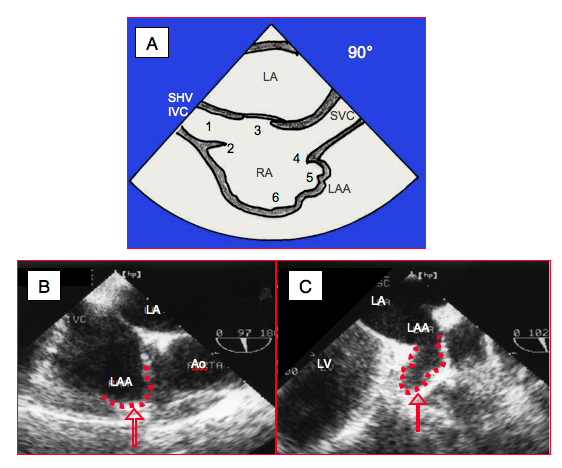

Figure 27.129: Anatomical criteria for the definition of right atrium (RA). A: Transesophageal bicaval view (90-100°). 1: IVC: inferior vena cava, SHV: supra-hepatic vein. 2: Eustachian valve. 3: fossa ovalis. 4: crista terminalis. 5: left atrial appendage (LAA). 6: trabeculated part of RA. B: right atrial appendage (bicaval view). C: left atrial appendage (2-chamber view).

The atria may also be distinguished by their specific anatomy. The RA has a short, obtuse and pyramidal atrial appendage. It is the site of the fossa ovalis of the atrial septum and receives the insertion of the Eustachian valve. Its wall is partially trabeculated. The boundary between the smooth part and the trabeculated part is marked by a crest (crista terminalis), which runs from one vena cava to the other (Figure 27.129). The LA, whose wall is completely smooth, has a long, pectinate, finger-shaped atrial appendage. Sometimes both atria exhibit the same anatomical characteristics, which is described as isomerism or mirror-image atria. Right isomerism (two RAs) is normally associated with the absence of the spleen (asplenia), while left isomerism (two LAs) is characterised by multiple spleens (polysplenia) [6].